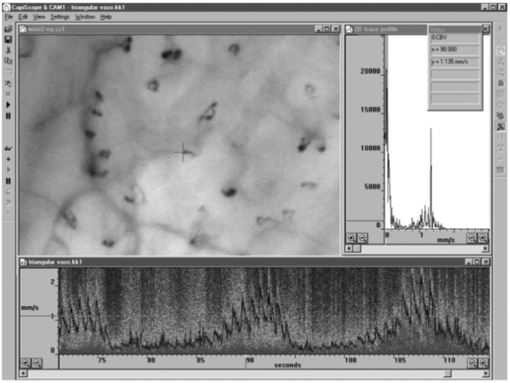

Standard image High-resolution imageNFC not only can help visualize the surface microvessels by microscopy, it can also be employed in combination with sophisticated methods in order to measure red blood cell velocity (figure 14), capillary pressure (i.e. cannulated capillaries using micropipettes and micropressure devices) (Morris et al 1996, Shore 2000) and transcapillary diffusion of a fluorescent tracer (sodium fluorescein injected intravenously—passage through vessels evaluated with a fluorescence microscope), thus allowing comprehensive physiological and pharmacological studies in humans (Bollinger and Fagrell 1990).

Figure 14. Skin capillaries from anterior aspect of wrist with KK Technology Capillary CAM1 anemometer system velocity recording at a single loop apex. Note the pulsatile component which is superimposed on low frequency vasomotor activity, www.kktechnology.com/cam1.html. (Courtesy of KK Technology.)